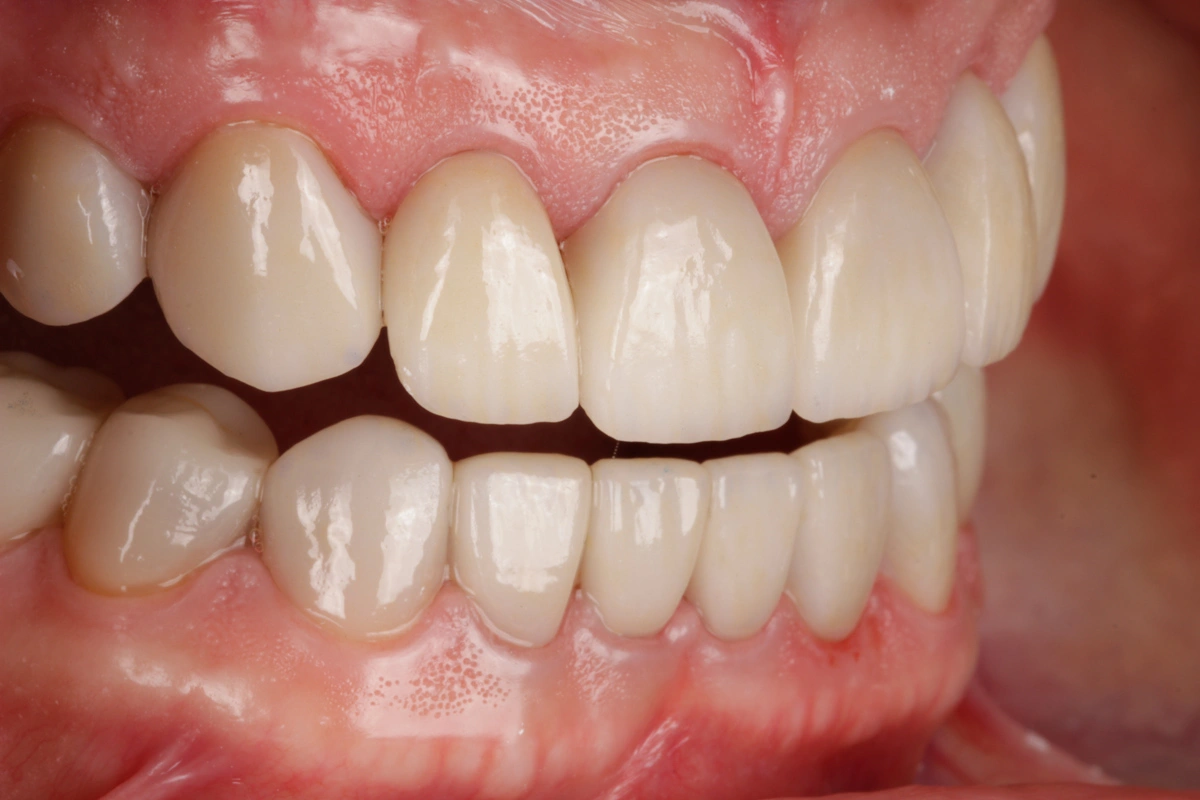

Tras realizar un estudio exhaustivo optamos por una rehabilitación completa con coronas, carillas e incrustaciones en disilicato de litio. Realizamos una prueba previa a la preparación de los dientes para establecer la longitud de los dientes definitivos.

Al finalizar el tratamiento, protegemos con una férula nocturna tipo Michigan.